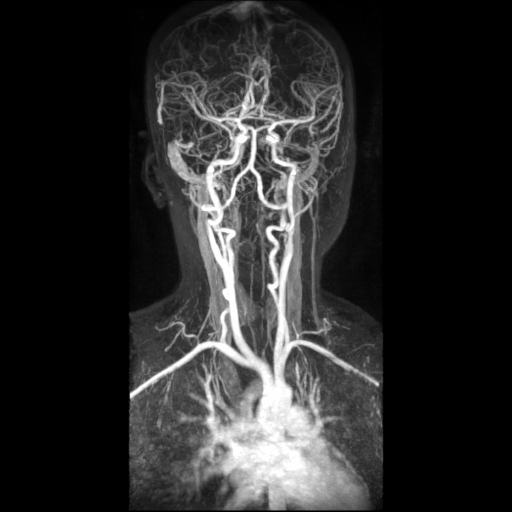

What can be done for carotid stenosis Depending severity of blockage treatments range from medicines angioplasty stenting surgery to clean out the plaque. Most other activities can be resumed. Thank you so very much. The nurse will usually ask if you would prefer want some sedative which may be good idea for are worried. There s not usually much day of procedure but it spreads second and lasts about week goes through colors [...]